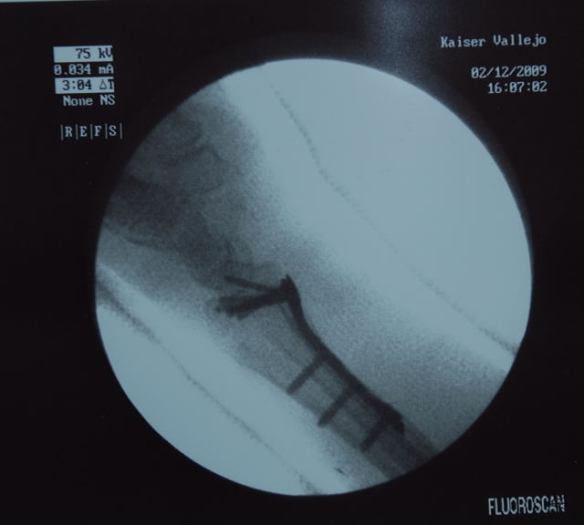

Here's what it looks like under the skin!

I think I counted 6 screws at the top.